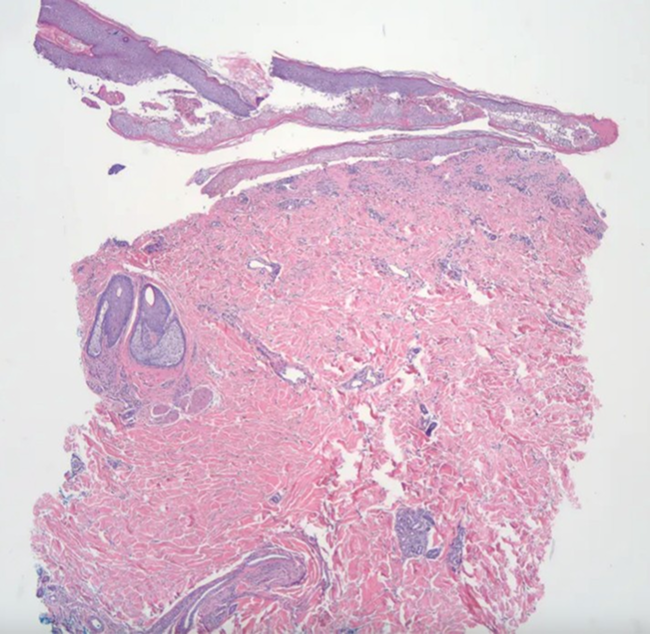

Figure 3: Denuded bisected punch biopsy of skin, which includes the superficial aspect of the subcutaneous tissue on H&E stain. There is a detached epidermal portion, which shows partial epidermal necrosis

Figure 4: Possible cytoid bodies noted in the detached epidermis